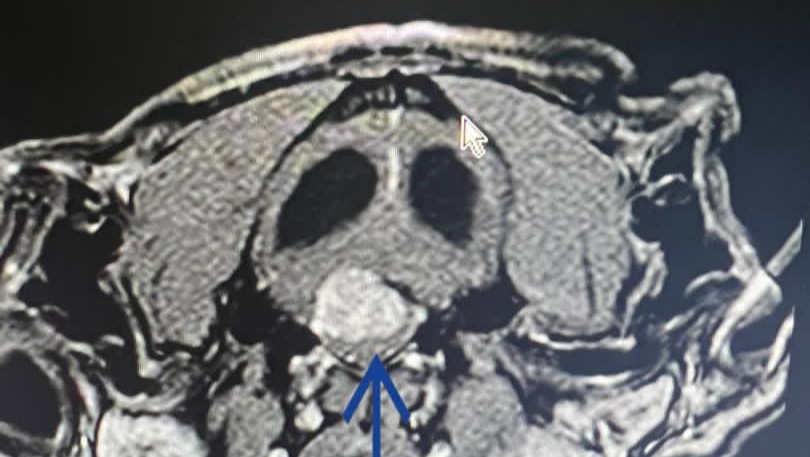

Dejaré anexadas fotos del presupuesto y de la resonancia magnética que le realizaron a Stitch en donde se observa el tumor (que está entre el cerebelo y la columna; una ubicación sumamente complicada de operar) y también se observa su tamaño (es como una pelota de Ping pong, es decir, muy grande). Eso le está causando obstrucción del líquido cefalorraquídeo y crea una hidrocefalia, la cual causa que Stitch no pueda caminar con normalidad, respirar, un síndrome vestibular y otras afecciones que poco a poco le costarán la vida.